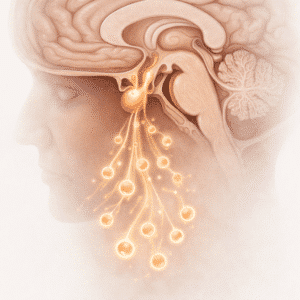

Mental & Emotional Support

What is mental and emotional support? Mental and emotional support…